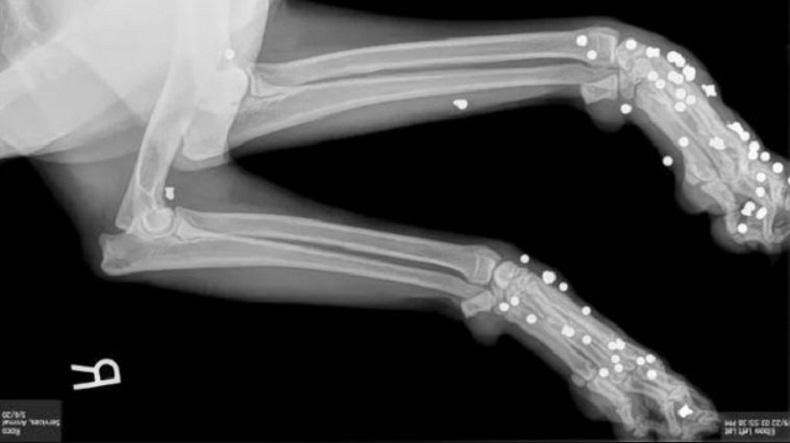

Perempuan di Florida ditangkap petugas setelah berulang kali menembak anjingnya dengan senapan angin. (Foto: HERNANDO COUNTY SHERIFF'S OFFICE)

TALLAHASSEE, iNews.id - Seorang perempuan di Florida ditangkap petugas setelah berulang kali menembak anjingnya dengan senapan angin. Ditemukan sekitar 170 peluru tertanam di bagian kaki kedua anjingnya.

Jamie Lynn Kujawa (37) ditahan awal pekan ini oleh polisi setelah dia menyerahkan dua anjing secara sukarela. Hasil dari x-ray mengungkapkan, lebih dari 170 peluru tertanam di tubuh kedua anjing.